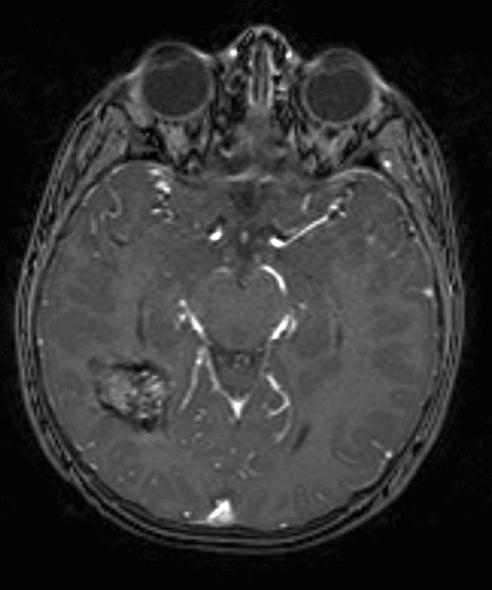

Kavernøst hemangiom, aksialt snitt 1

kavernøst hemangiom 1

Gjengitt med tillatelse av Radiologisk avdeling, Universitetssykehuset Nord-Norge